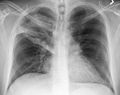

A chest X-ray showing a very prominent wedge shaped pneumonia in the right lung. | |

وعن طريق السماعة الطبية، يستطيع الطبيب أن يسمع أصواتًا مميزة آتية من الرئة تدل على وجود المرض. ويمكن لأشعة إكس (الأشعة السينية)، والاختبارات المعملية، أن تؤكد صحة التشخيص. أما تحديد نوع الميكروب المسبب للمرض، فإنه يتم عن طريق الاختبارات المعملية، إذ يقوم العامل الفني المتخصص بفحص عينة من بلغم المريض تحت المجهر. كما يعالج البلغم أيضًا بطرق مختلفة، حتى يمكن تنمية الكائن العضوي المُسبِّب للعدوى داخل المعمل، بحيث يمكن التعرف عليه.